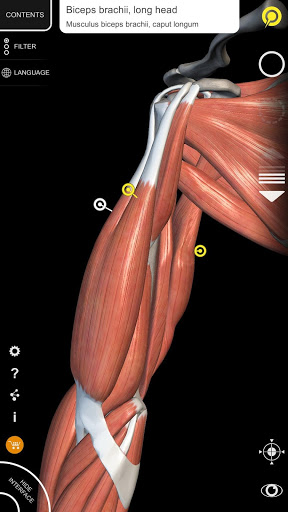

"Anatomy 3D Atlas" vous permet d'étudier l'anatomie humaine de manière simple et interactive.

Grâce à une interface simple et intuitive, il est possible d'observer chaque structure anatomique sous n'importe quel angle.

Les modèles anatomiques 3D sont particulièrement détaillés et avec des textures jusqu'à une résolution de 4k.

• Visualisation des muscles à travers des niveaux de couches depuis les plus superficielles jusqu'aux plus profondes

• Description des muscles : origine, insertion, innervation et action